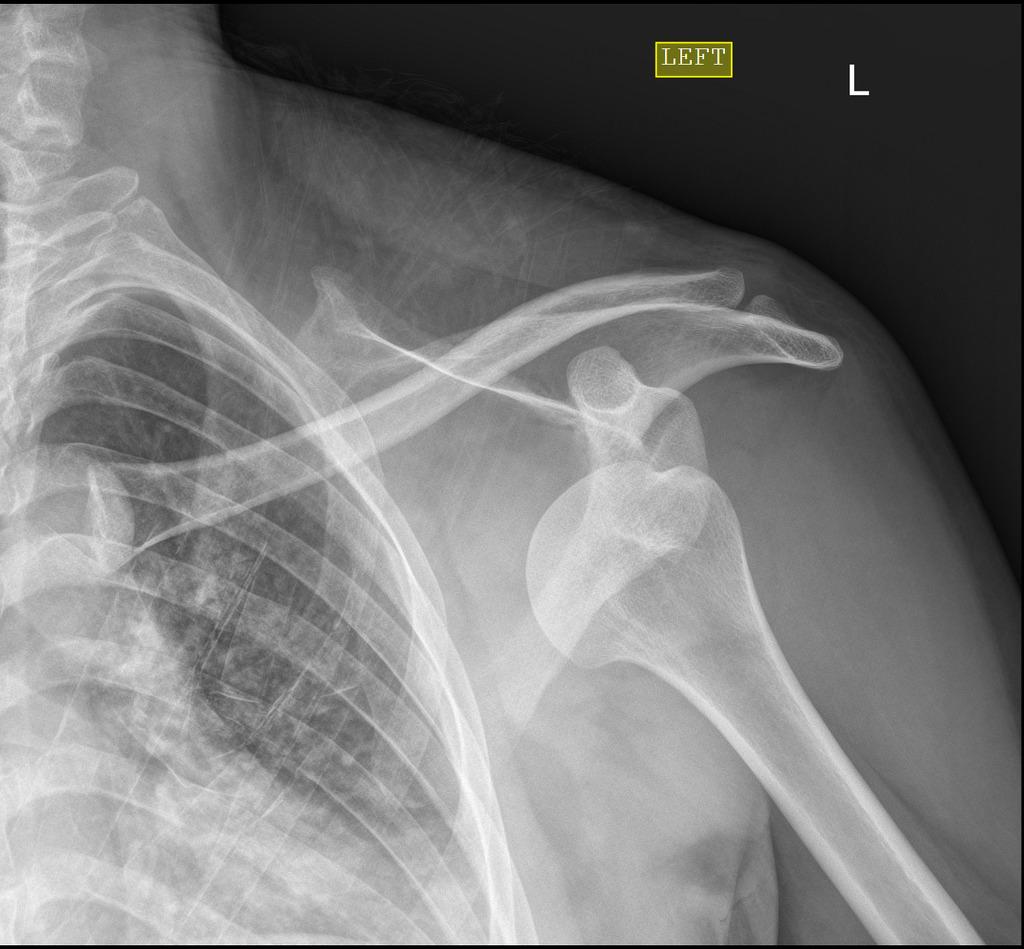

48歲陳姓女患者,因摔倒造成右肩膀疼痛並難入眠,一開始被認為只是單純的右肩脫臼,被「喬」了幾次卻都無法成功。最後至醫院骨科看診,經醫師診視後,安排進行電腦斷層掃描檢查,確定患者肩膀非單純脫臼,而是右肩前盂唇脫落,因此必須進行手術治療。

個案右肩關節前唇整片軟體組織脫落,故造成不穩定性關節,這種不穩定性關節是無法用徒手復位治療,必須接受傳統開放性復位手術,但傳統開放式手術又會破壞大片軟體組織,所以王叔昂醫師建議使用電腦斷層術中定位協助盂唇微創復位手術,不僅傷口小(僅有1公分左右)、血流少,並且手術時間與恢復時間皆縮短,讓患者盡早能恢復到日常生活。

經由複合式手術室的電腦斷層術中定位系統輔助,精準地植入螺釘將脫落的整片盂唇固定復位,手術成功復原良好,患者住院三天即返家休養。